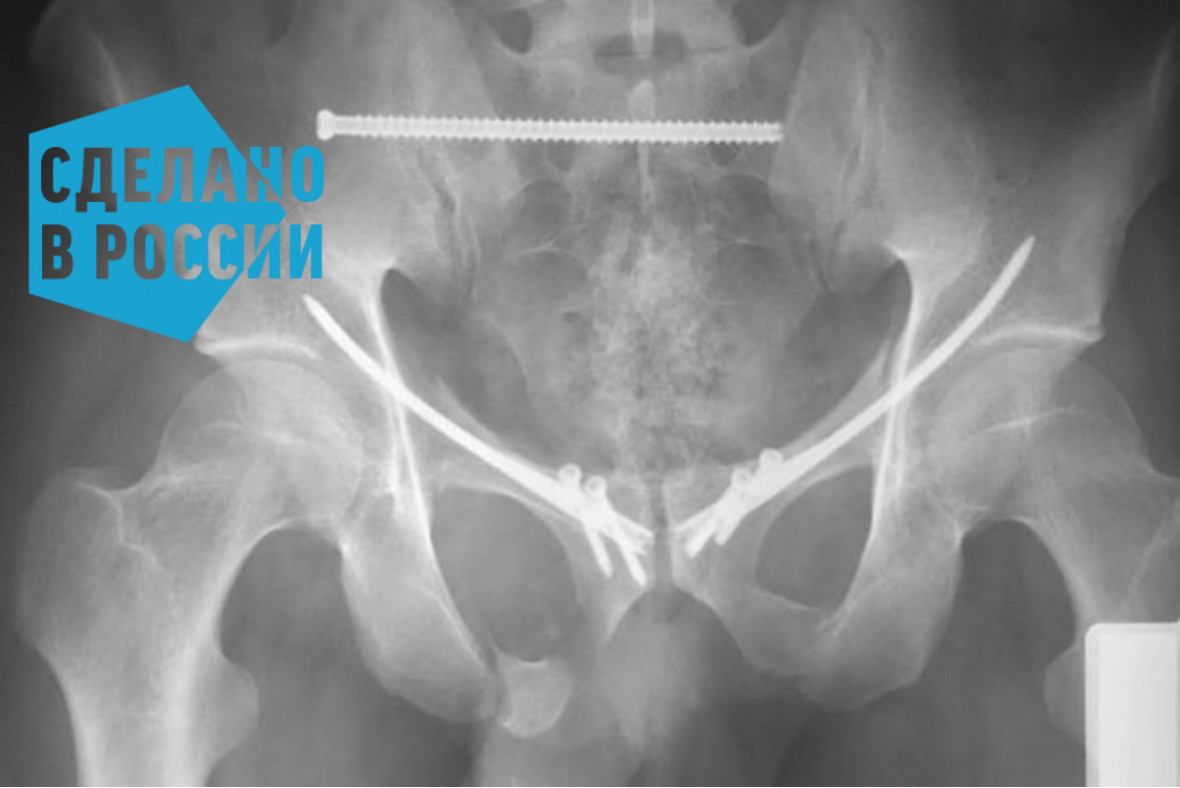

Остеосинтез перелома лонной кости штифтом с блокированием . . .

Перелом костей таза . Нестабильные переломы ветвей лонной кости - достаточно частое явление при повреждениях переднего полукольца таза и, для более благоприятного клинического исхода лечения, требуют фиксации .